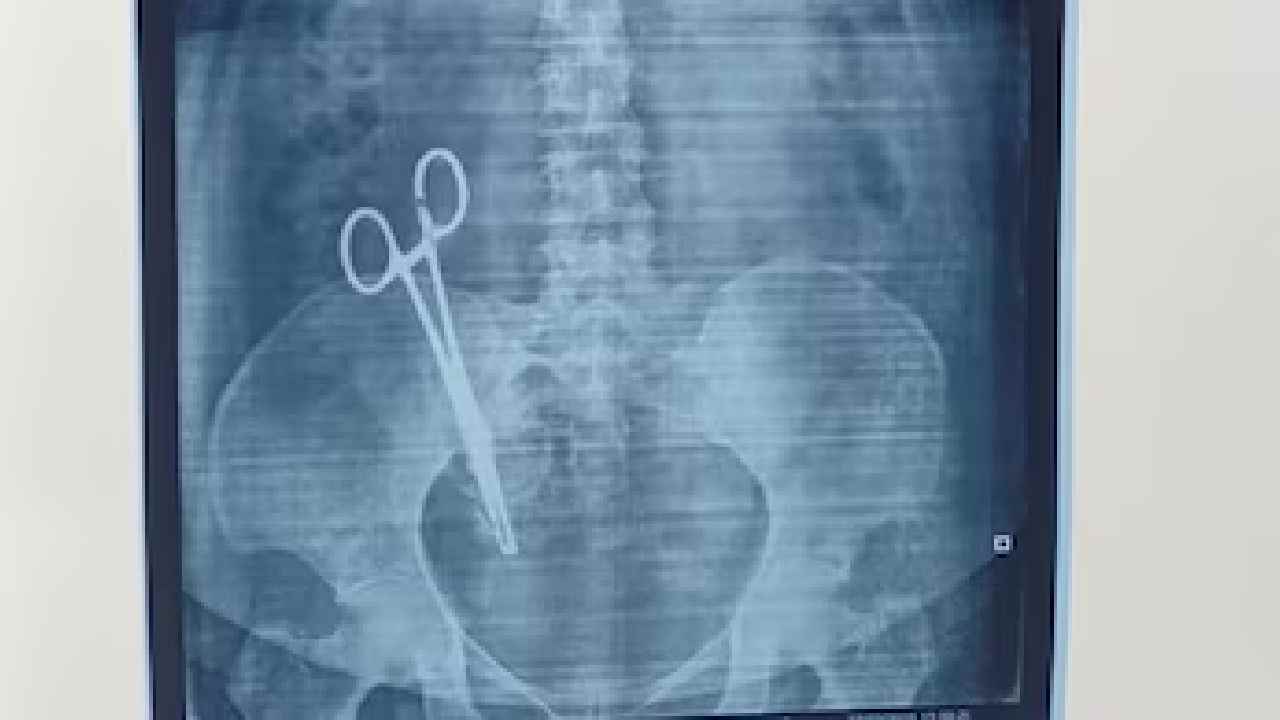

• 17 ఏళ్లుగా మహిళ కడుపులో కత్తెర..

• సిజేరియన్ ఆపరేషన్ సమయంలో వైద్యుల నిర్లక్ష్యం..

• కడుపు నొప్పి కారణంగా ఇటీవల ఎక్స్ రే తీయడంతో షాక్..

• సర్జరీ చేసి కత్తెరను తొలగించిన వైద్యులు..

Scissors in stomach: 17 ఏళ్లుగా కడుపునొప్పితో బాధపడుతున్న ఓ మహిళకు ఎక్స్-రే తీసి చూడటంతో షాక్‌కి గురయ్యారు. ఆమె కడుపుతో ఒక కత్తెర ఉండటాన్ని డాక్టర్లు గమనించారు. ఇన్ని ఏళ్లుగా ఈ విషయం ఎలా తెలియలేదని ఒకింత ఆశ్చర్యానికి గురయ్యారు. మహిళ సిజేరియన్ సమయంలో కడుపులో కత్తెరను మరించిపోయినట్లు గుర్తించారు. లక్నోకి చెందిన బాధితురాలు సంధ్యా పాండేకు ఫిబ్రవరి 28, 2008లో ఒక బిడ్డ పుట్టింది. ఆ సమయంలో ‘‘షీ మెడికల్ కేర్’’ నర్సింగ్ హోమ్‌లో సీ-సెక్షన్ ఆపరేషన్ చేయించుకుంది. ఆ సమయంలోనే కత్తెరను కడుపులో వదిలేసినట్లు గుర్తించారు.

అయితే, గత 17 ఏళ్లుగా సంధ్యా కడుపు నొప్పితో బాధపడుతోంది. వైద్యుల నిర్లక్ష్యం కారణంగా ఈ బాధను అనుభవిస్తూ వచ్చయింది. దీనిపై ఆమె భర్త అరవింద్ కుమార్ పాండే పోలీసులకు ఫిర్యాదు చేశాడు. గత కొన్నేళ్లుగా వైద్యులును సంప్రదిస్తున్నప్పటికీ పరిస్థితిలో పెద్దగా మార్పు రాలేదు. ఇటీవల లక్నో మెడికల్ కాలేజీలో సాధారణ వైద్య పరీక్షల్లో భాగంగా ఎక్స్ రే తీసి చూడగా ఆమె పొత్తికడుపులో కత్తెర ఉన్నట్లు గుర్తించారు.

ఈ విషయం తెలిసిన తర్వాత, ఆమెకు లక్నోలోని కింగ్ జార్జ్ మెడికల్ యూనివర్సిటీ (KGMU)లో చేర్చారు. మార్చి 26న సంక్లిష్టమైన సర్జరీ చేసి కత్తెరనున బయటకు తీశారు. ఈ ఆపరేషన్ సవాలుతో కూడుకున్నదని డాక్టర్లు చెప్పారు. ప్రస్తుతం మహిళ పరిస్థితి బాగానే ఉందని, ఆమె డిశ్చార్జ్ అయి ఇంటికి తిరిగి వెళ్లినట్లు చెప్పారు.